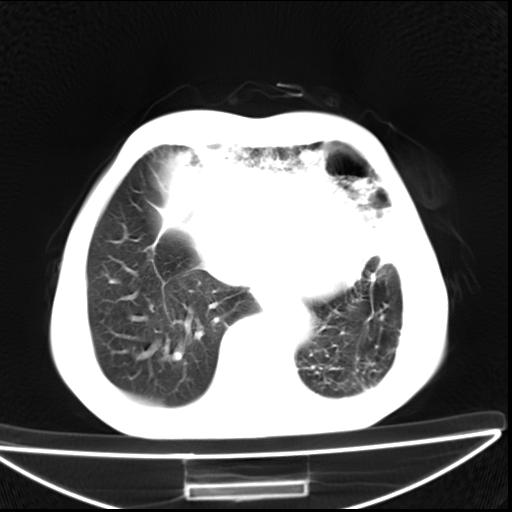

男  70岁,发烧咳嗽4天。盗汗,消瘦。无痰中带血丝,以前有肺tb病史,ct见,双肺tb,左侧胸廓塌陷,左胸膜肥厚粘连。纵隔移位,右侧胸腔积液,大家说说那个心影前左肺舌叶除了肺大炮还有炎症还是干酪性肺炎?有占位吗?我看纵隔淋巴结也大。

1)两肺继发性肺结核并左肺上叶肺不张,支气管扩张。2)双侧胸膜炎(胸膜增厚+少量胸腔积液)。

双肺继发性肺结核伴部分左肺毁损!

双肺继发性肺结核伴部分左肺毁损。